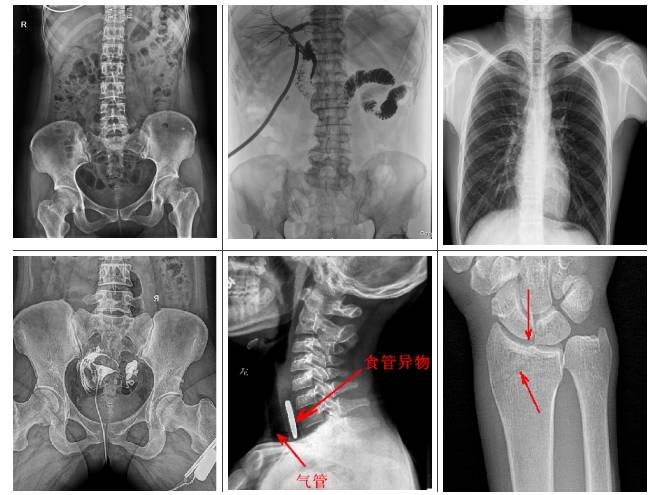

懸吊雙板DR是集拍片、造影于一體,可檢查多類疾?。?/p>

1.可檢查患者的呼吸系統(tǒng)疾病,比如是否有肺炎、肺腫瘤、肺結(jié)核、肺膿腫、胸腔積液以及氣胸等。

2.可檢查縱隔以及心臟系統(tǒng)的疾病、骨關(guān)節(jié)系統(tǒng)的疾病。

3.可做泌尿系統(tǒng)造影,子宮輸卵管造影、胃腸道造影,比如做鋇餐的檢查,觀察胃腸道是否有炎癥、腫瘤以及潰瘍等。

4.有職業(yè)病體檢篩查塵肺病功能,及發(fā)現(xiàn)區(qū)別肺部小結(jié)節(jié)功能。

普利德懸吊雙板DR采用動靜態(tài)雙板配置,可實現(xiàn)毫秒級選板切換,專板專用,高效專業(yè)??晒└骷夅t(yī)院進行人體頭部、頸部、胸部、腹部、腰椎、四肢等部位的臥位、正位、側(cè)位、斜位的數(shù)字化攝影、透視及造影檢查;適用于各級醫(yī)院臨床各個科室,滿足放射科、體檢中心、影像中心、內(nèi)科、外科

、急診科、骨科、創(chuàng)傷科、消化科等科室的多種臨床檢查需求。